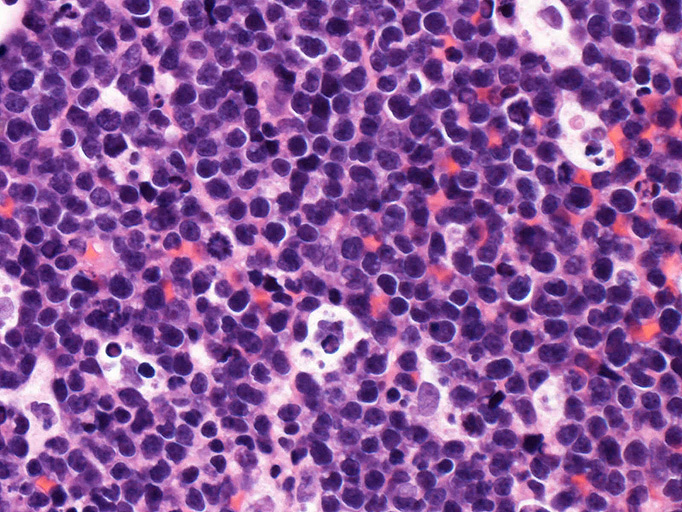

組織・細胞病理所見

エコーガイド下肝腫瘤針生検組織

尾状葉の腫瘍から16G, 11mm穿刺針で5mm, 2mmの組織を採取した。2mmの組織は線維組織と肝組織で腫瘍細胞を含んでいなかった。穿刺針洗浄液をkaryotypeに提出する。

liver biopsy x10liver biopsy x20生検組織スタンプ標本